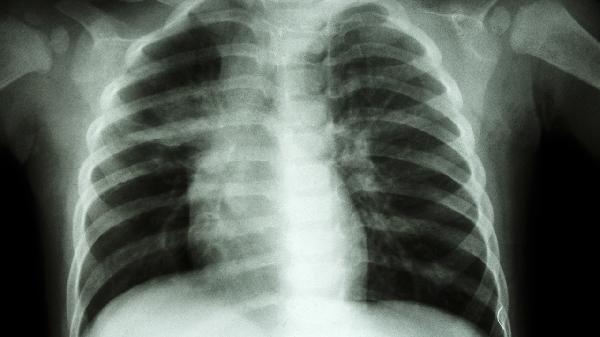

家长应定期观察儿童胸廓发育形态,2岁前每3个月测量一次胸围。保证每日户外活动1-2小时促进维生素D合成,饮食中适量增加乳制品、深绿色蔬菜等含钙食物。避免让婴幼儿长期保持蜷缩睡姿,选择硬板床有助于胸廓正常发育。发现胸骨明显前突或伴随呼吸困难时,应及时至儿童骨科或胸外科就诊,通过X线或CT评估畸形程度。轻度鸡胸可通过运动康复改善,中重度需在青春期前完成矫形干预以获得最佳效果。